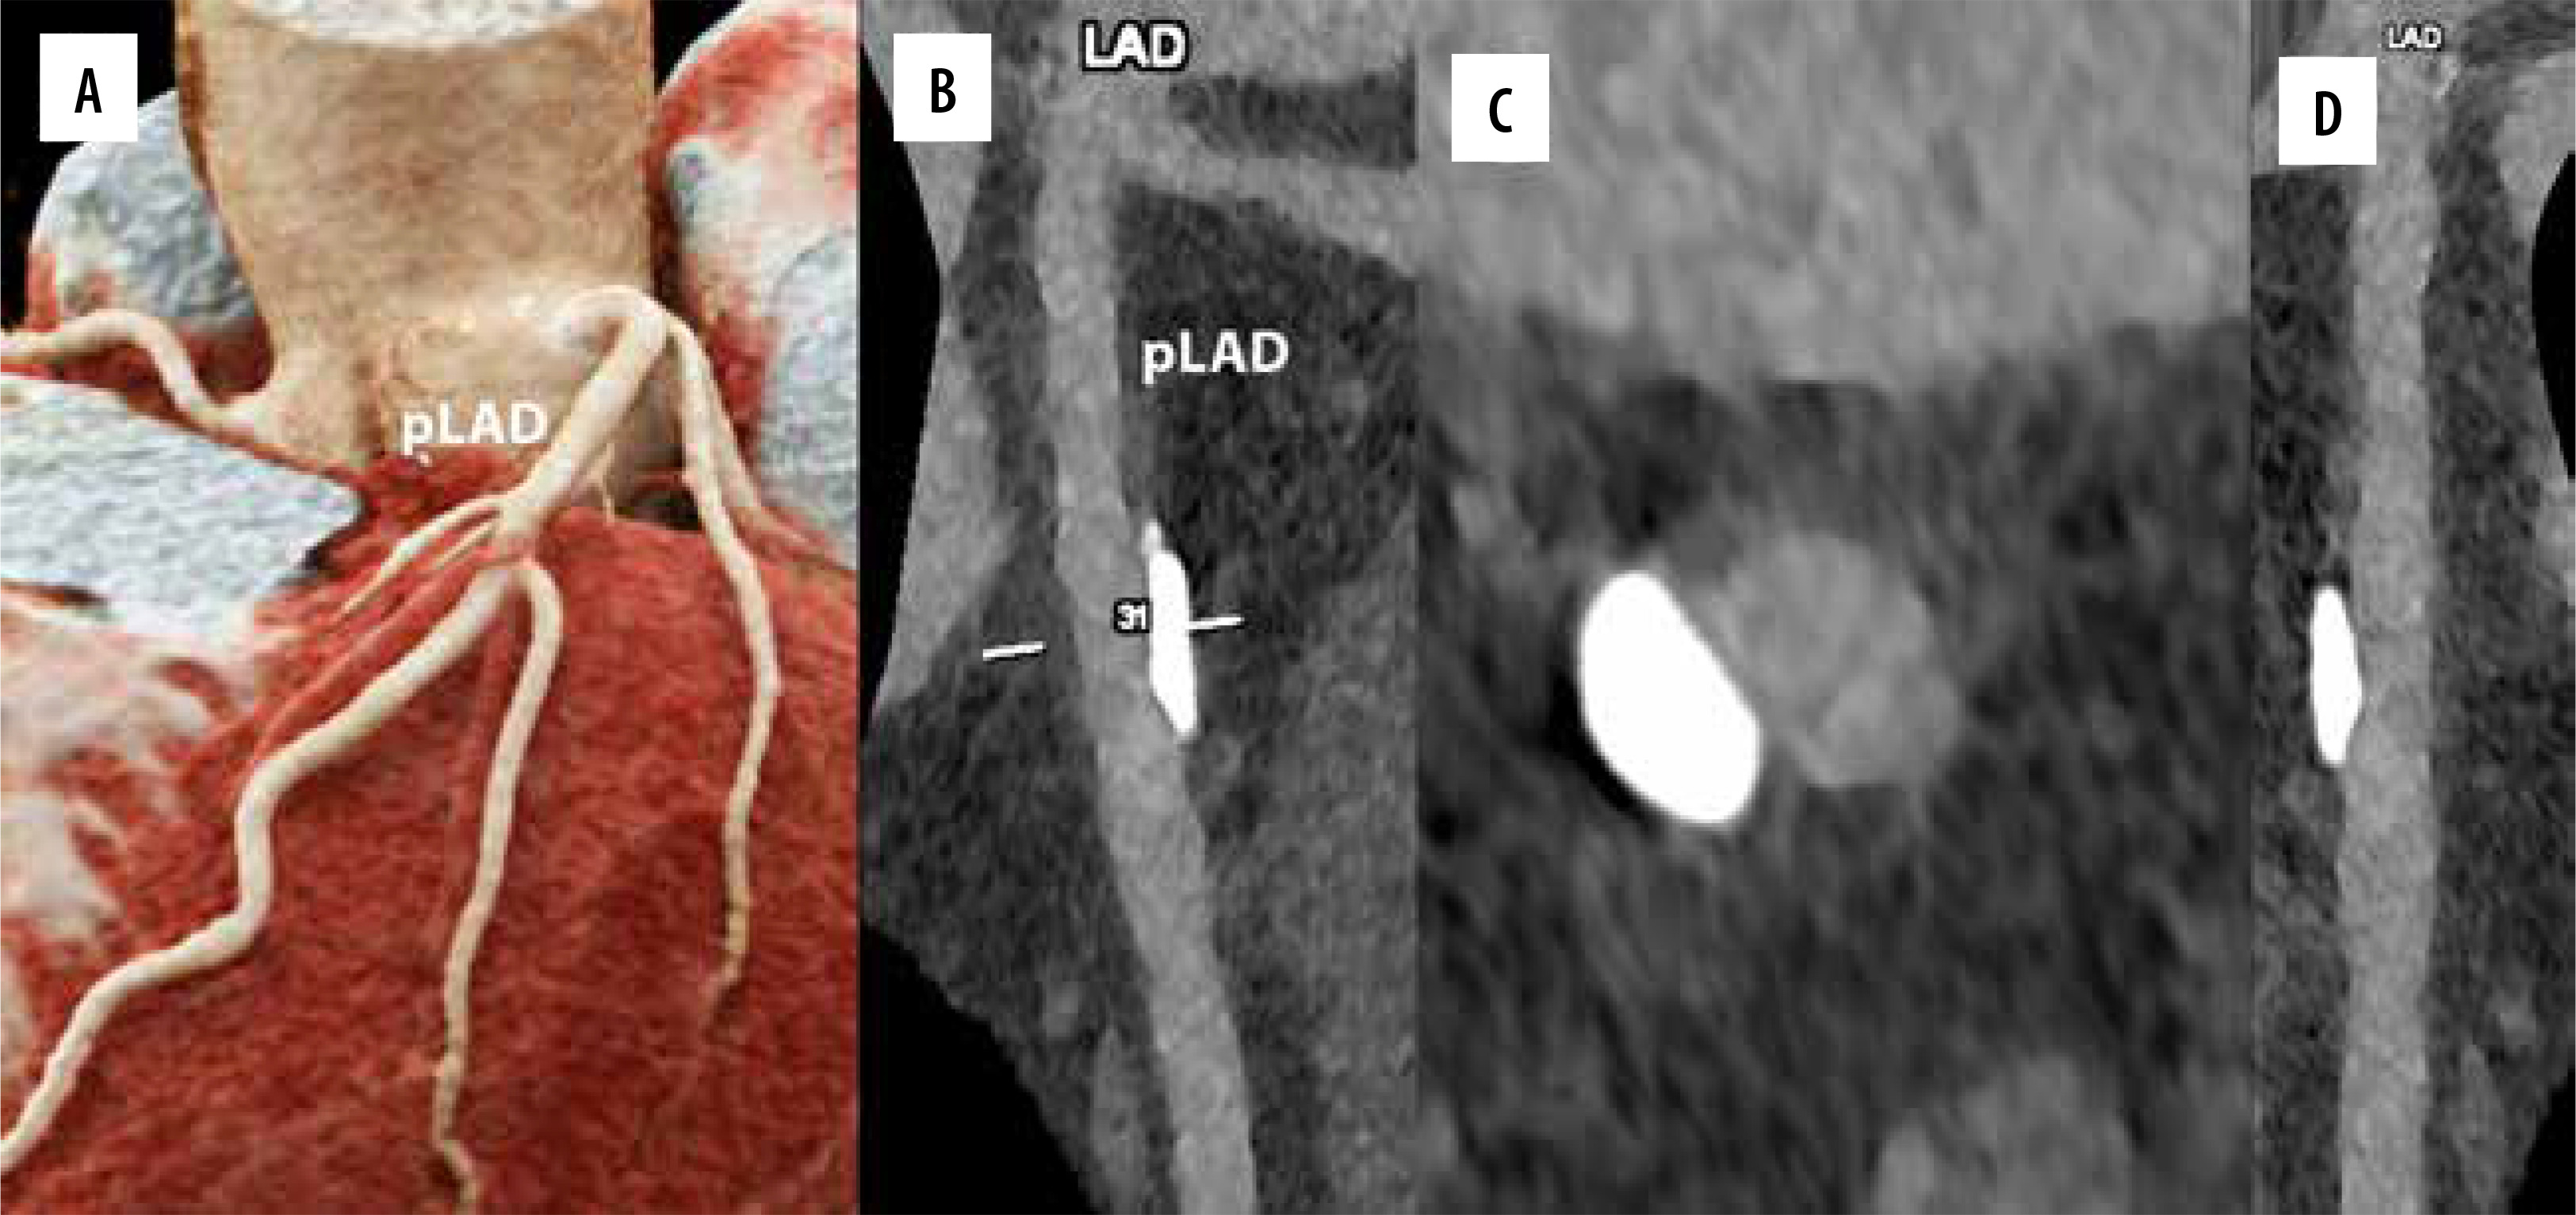

PCD-CT eliminates beam-curing artifacts. By obtaining VMIs, the optimum CNR and iodine concentration maps can be obtained [12,36]. These data were used to distinguish intravascular contrast media from calcified plaques in the carotid arteries [31]. CT imaging may be hindered by artifacts in patients with calcified plaques, metallic implants, clips, and/or coils [37]. Metallic artifact reduction algorithms and VMIs have enhanced the image quality in PCD-CT [1,38,39]. This is especially crucial when assessing small stents made of highly attenuating materials. Recent research indicates that PCD-CT provides greater visibility and resolution of coronary lesions (Figure 4) [40,41]. Images acquired by PCD-CT showed a significant reduction in metal artifacts and an increase in dose efficiency compared with EID-CT [42,43]. Additionally, fewer streaking artifacts were observed in PCD units [44].

Figure 4

Cardiac/coronary photon-counting computed tomography (PCCT) example of a diseased coronary artery treated with an intracoronary stent. In the 2 main panels a 3D Cinematic Rendering (A), a curved multiplanar (MPR) reconstruction along the central lumen line of proximal (B; pLAD) and mid left anterior descending (B; stent). The scan was performed on a commercial whole-body dual-source photon-counting CT scanner (Naeotom Alpha, Siemens Healthineers, Forchheim, Germany) with 0.2 mm slice thickness, 0.1 mm reconstruction increment, and FOV 140 mm; the scan was performed with retrospective ECG gating with tube current modulation. In this case, the pLAD shows severe non-obstructive disease with non-calcified and calcified components down to the proximal edge of the coronary stent; the stent is perfectly patent and visible; stent struts are perfectly visible, and it is quite easy to assess the proximal calcification on the outer contour of the stent determining no issues in terms of intrastent lumen assessment. The images are displayed with a resolution matrix of 1024 × 1024 pixels on the source axial reconstructions with a kernel filtering of Bv76 (vascular kernel medium-sharp) and with the maximum intensity of quantum iterative reconstruction (QIR 4). The actual displayed resolution is 0.1 mm (100 microns)

In individuals with renal insufficiency, reducing the iodine dose is crucial. Low monochromatic image usage in dual-energy CT and reduced tube voltage in conventional CT are 2 techniques for reducing the iodine load [45-47]. PCD-CT generates monoenergetic reconstructions through energy-resolved detection and is more useful for iodine-based contrast agent detection than conventional CT detectors [48]. Iodine-specific applications might enhance the quality of coronary artery imaging (Figure 5) [31]. VMIs obtained with 40-60 keV were the best for the detection of pulmonary embolism by quantitative metrics [48]. VMIs at 60–70 keV provided better image quality in terms of vessel contrast [15].

Figure 5

Cardiac/coronary photon-counting detector–computed tomography (PCD-CT) example of mildly diseased coronary arteries. In the 4 main panels a 3D cinematic rendering (A), a curved multiplanar (MPR) reconstruction along the central lumen line of proximal left anterior descending (B; pLAD), an MPR axial/cross-sectional view of the same vessel (C) and a stretched MPR view are displayed. The scan was performed on a commercial whole-body dual-source photon-counting CT scanner (Naeotom Alpha, Siemens, Forchheim, Germany) with 0.2 mm slice thickness, 0.1 mm reconstruction increment, matrix 1024 × 1024, kernel Bv60, and FOV 140 mm; the scan was performed with retrospective ECG gating with tube current modulation. In this case, the segments of coronary arteries show a large singular eccentric calcification of the pLAD with no effect on lumen patency (no lumen diameter or area reduction) and it is displayed with a resolution matrix of 1024 × 1024 pixels on the source axial reconstructions with a kernel filtering of Bv60 (vascular kernel medium-sharp) and with maximum intensity of quantum iterative reconstruction (QIR 4). The actual displayed resolution is 0.1 mm (100 microns)